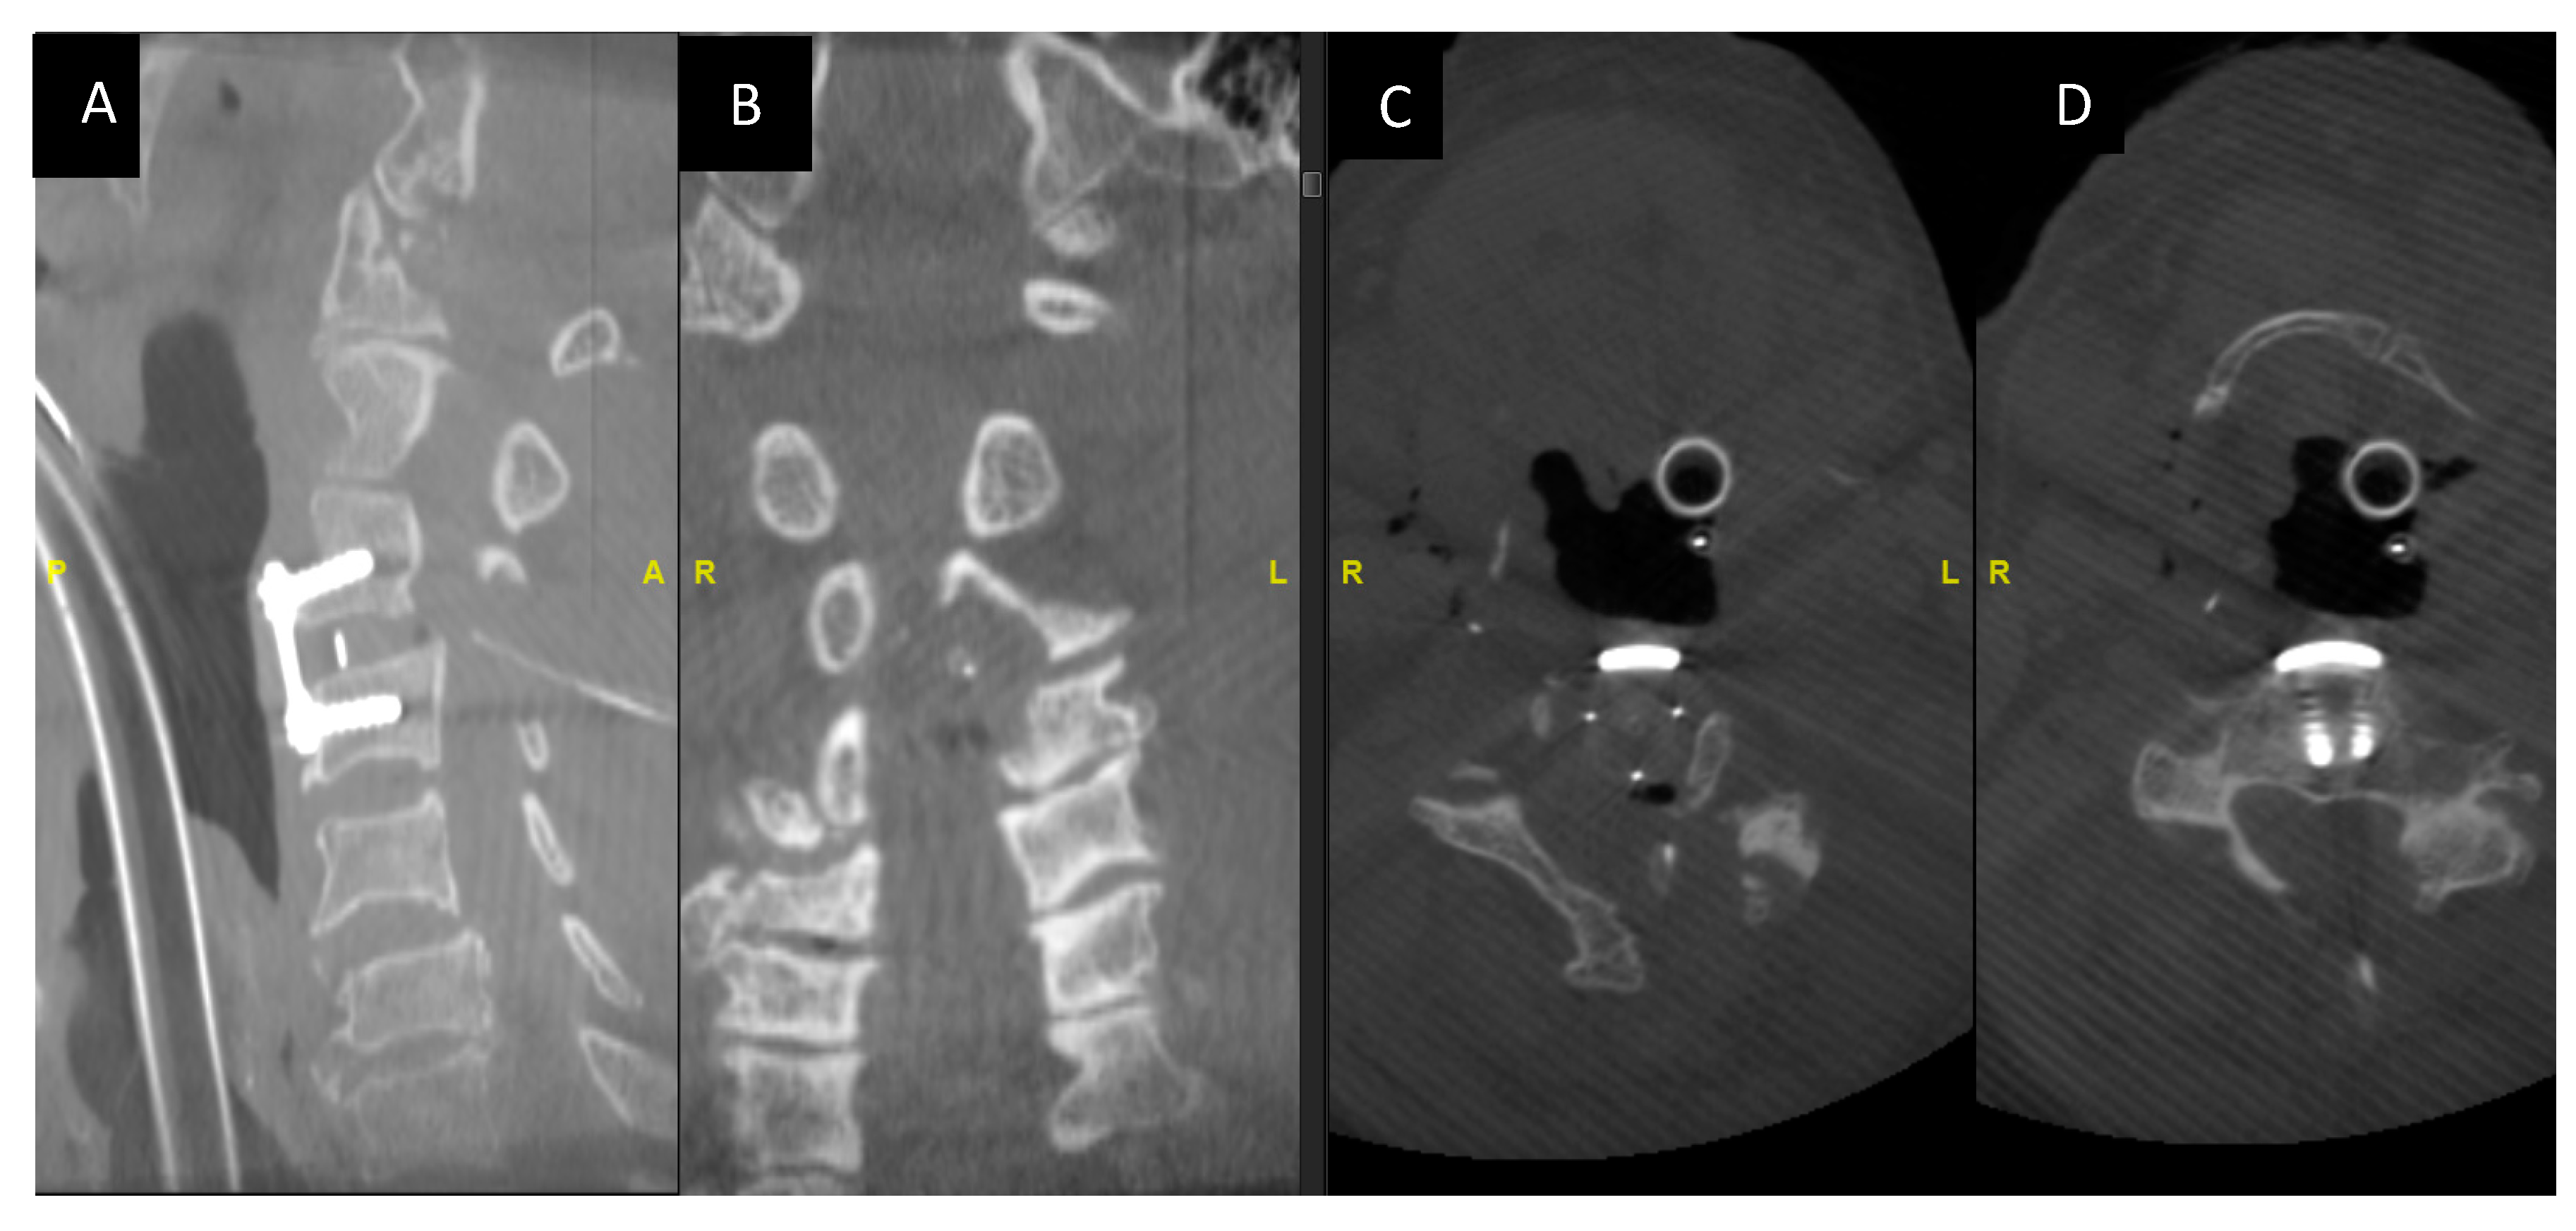

After the completion of decompression, we perform an intraoperative 3-D CT imaging using an O- Arm to radiologically confirm the adequacy of decompression (Figure 6A–D).

Figure 6.

Intraoperative O-arm CT images showing the adequacy of decompression and the implant position. (A,B) Intraoperative O arm imaging sagittal and coronal images post-decompression. (C,D) Axial cuts at the C3 level post-decompression.